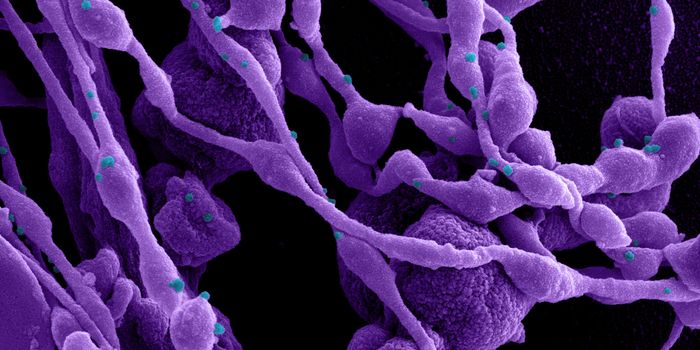

AUG 19, 2020Cell & Molecular BiologyAs the pandemic virus, SARS-CoV-2 continues to cause tens of thousands of new cases of COVID-19 every day in the United ...

APR 27, 2020MicrobiologyThe pandemic virus that causes COVID-19 has now infected nearly 3 million people, and killed over 200,000.

MAY 10, 2021MicrobiologyThe pandemic virus SARS-CoV-2 has changed the world in devastating ways, taking hundreds of thousands of lives & new var ...